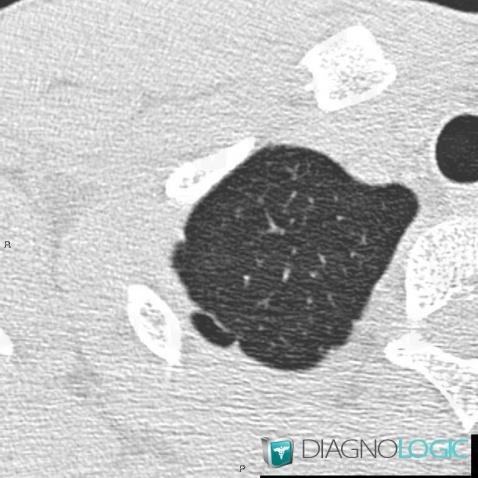

Bleb, Parenchyme pulmonaire, Scanner

Voici les informations spécifiques à l'image clé ci dessus:

- Diagnostic Bleb, Localisation(s) Parenchyme pulmonaire, comportant les gammes Lésions kystiques pulmonaires multiples